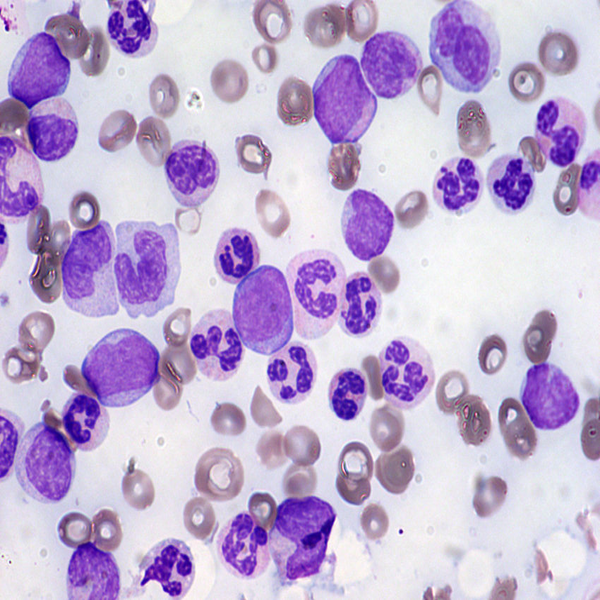

- General and specialized tissue and cell staining

- Perform tunnel technique to evaluate apoptosis

Histological methods includes sample processing in the pathology laboratory, preparation of the slide and its examination under a microscope, sample fixation, molding, microtome cutting, staining and assembly of the slides.